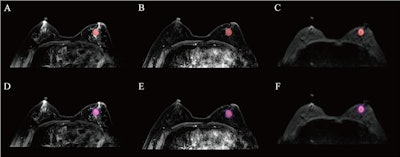

The results depict tumor segmentation. an example of HER2 positive breast cancer is shown: (A), (B), and (C) represent the segmentation results of the entire tumor region on the T2WI, DCE-MRI, and DWI sequences, respectively; (D), (E), And (F) show the segmentation results of the intratumoral region combined with 3 mm peritumoral area on the T2WI, DCE-MRI, and DWI sequences, respectively.The results depict tumor segmentation. an example of HER2 positive breast cancer is shown: (A), (B), and (C) represent the segmentation results of the entire tumor region on the T2WI, DCE-MRI, and DWI sequences, respectively; (D), (E), And (F) show the segmentation results of the intratumoral region combined with 3 mm peritumoral area on the T2WI, DCE-MRI, and DWI sequences, respectively.Available for reuse under Creative Commons license (Attribution 4.0 International CC BY 4.0 Deed)